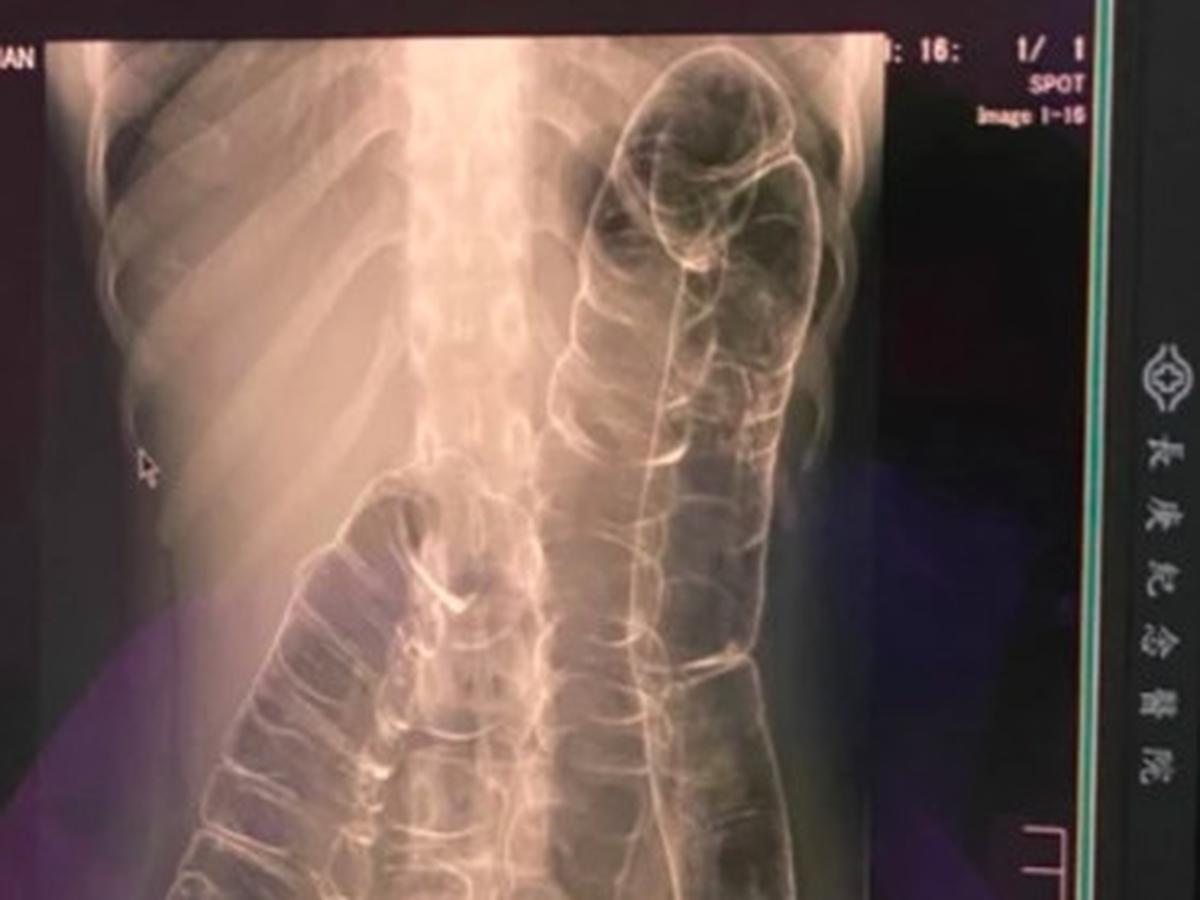

Sering Sembelit Wanita Ini Syok Lihat Rontgen Usus Besarnya Sampai Ke Jantung Citizen6 Liputan6 Com